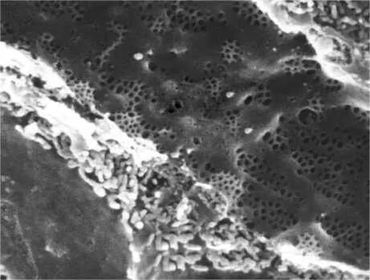

SEM of Fenestrated sinusoid of Liver

A : Space of Disse B : Hepatocyte C : fenestrea of epithelial cells ( Sieve plate)